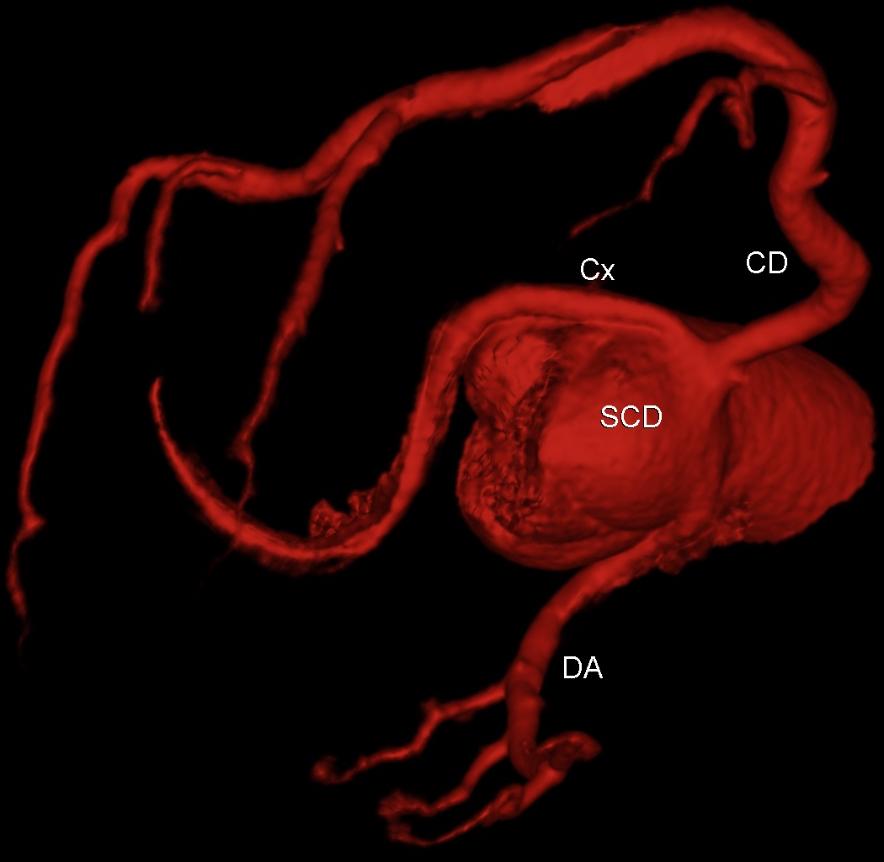

Enquanto a Copa do Mundo 2022 começava no Catar, era publicada no JACC uma revisão campeã sobre o estado da arte na abordagem da doença de tronco da coronária esquerda significativa, isto é, com esten…

Segundo a sub-análise publicada recentemente no JACC Adv sobre o estudo DISCHARGE, sim1.Esse ensaio clínico se propôs a avaliar se a angiotomografia de coronárias seria superior ao cateterismo na ava…